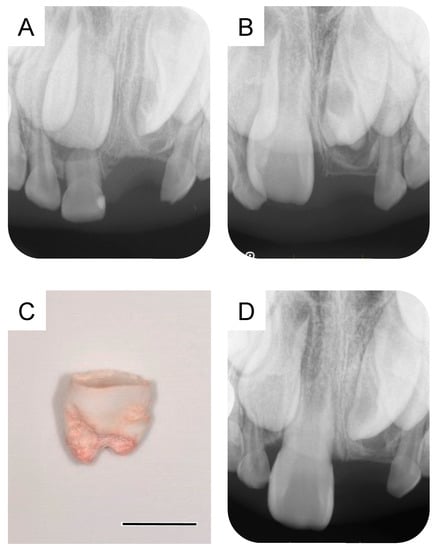

At 5 years and 5 months of age, a supplemental supernumerary tooth (first supernumerary tooth) was detected near the permanent maxillary left central incisor (Figure 1A). This supernumerary tooth gradually erupted and was extracted 6 months later (Figure 1B).

Figure 1. Extraction of the first supernumerary tooth. (A) Periapical radiograph of the first supernumerary tooth detected at the age of 5 years and 5 months. (B) Extracted first supernumerary tooth at the age of 5 years and 11 months. Scale bar: 5 mm.